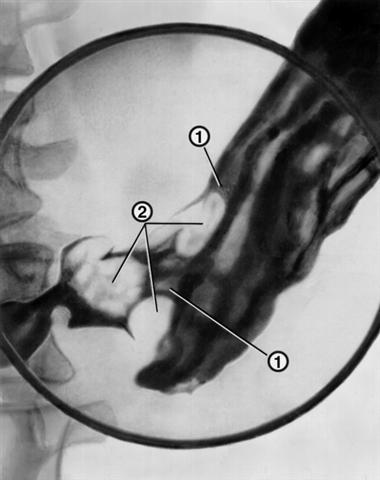

Рис. 4. Прицельная рентгенограмма желудка (с компрессией) при экзофитной форме роста рака антрального отдела: складки слизистой оболочки утолщены, обрываются (1); определяются множественные неправильной формы дефекты наполнения (2).